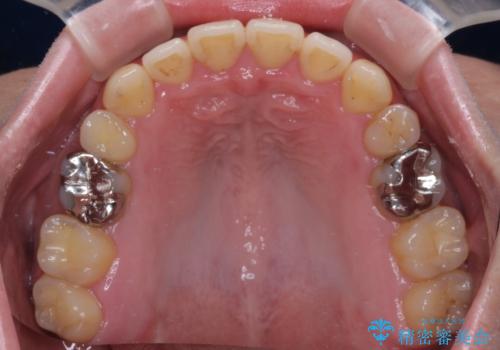

- 抜歯矯正の後戻りを気にして来院された患者様です。

舌の突出癖によるオープンバイトになり、前歯の叢生が後戻りしていました。

舌のトレーニングを行いながら、インビザラインを用いて矯正治療を行うこととしました。

インビザラインの特性を活用して奥歯の咬み合わせを圧下させることで、前歯のオープンバイトを改善さえることができました。